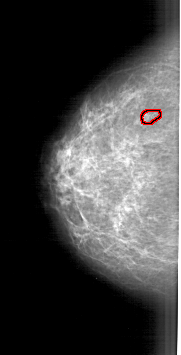

FILE: A_1905_1.LEFT_MLO.OVERLAY

TOTAL_ABNORMALITIES 1

ABNORMALITY 1

LESION_TYPE CALCIFICATION TYPE PLEOMORPHIC DISTRIBUTION CLUSTERED

ASSESSMENT 4

SUBTLETY 3

PATHOLOGY MALIGNANT

TOTAL_OUTLINES 1

BOUNDARY